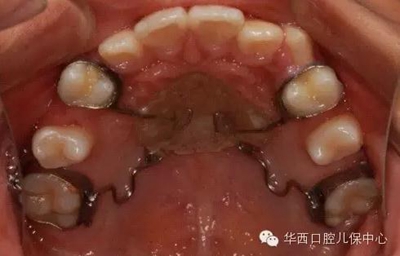

圖為幾種活動(dòng)擴(kuò)弓矯治器的設(shè)計(jì)